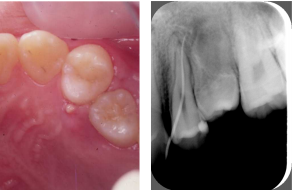

18.下圖為右側上顎第一大臼齒手術前與手術後的X光片,則其所接受的治療術式為何? (A)根尖切除術(apicoectomy) (B)半切斷術(hemisection) (C)牙根切斷術(root amputation) (D)蓄意再植術(intentional replantation)

25.10歲男童因左上顎小臼齒區腭側牙齦腫脹1週而來求診,臨床檢查發現第一小臼齒對冷刺激有感覺,但第二 小臼齒對冷刺激沒有反應,電髓活性檢查(electric pulp test)時小臼齒都有輕微的酸痛感,腭側觸診檢查時 兩顆小臼齒皆有明顯不適,敲診檢查發現第一小臼齒有輕微不適感,而第二小臼齒有明顯的敲痛症狀,患齒 的臨床影像紀錄與放射線學檢查結果如下圖所示。則下列診斷何者最有可能?

(A)第一小臼齒慢性根尖膿腫(chronic apical abscess) (B)第二小臼齒慢性根尖膿腫(chronic apical abscess) (C)第一小臼齒急性根尖膿腫(acute apical abscess) (D)第二小臼齒急性根尖膿腫(acute apical abscess)